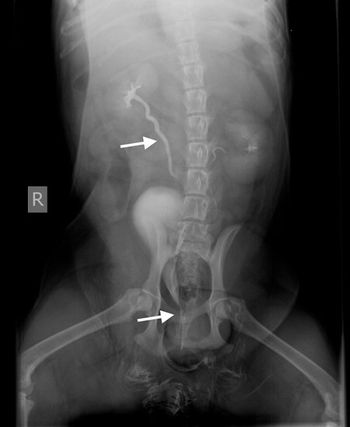

Veterinary radiologist Dr. Anthony Pease explains why contrast agents are a quick, easy way to examine the urinary tract